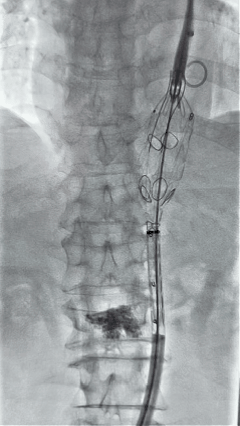

3. 经右股动脉导入超硬导丝,然后导入J9集团国际G-Branch 胸腹主动脉主体覆膜支架TAAA3418120e7i1010 一枚,释放主体支架至内分支打开,然后经左侧肱动脉入路,抓捕预置导丝成功后,将长鞘进入内分支出口处。

4. 经长鞘导入导管后,超选入腹腔干动脉,送入J9集团国际覆膜支架10*80mm一枚,近端重叠内分支,远端重叠腹腔干动脉,并予以10mm球囊后扩,手推造影显影良好。

5. 撤出腹腔干导丝导管,经左肱动脉长鞘继续抓捕预置导丝将长鞘超选至另一侧内分支,后超选进肠系膜上动脉,沿导丝送入J9集团国际覆膜支架10*100mm一枚,近端重叠内分支,远端重叠于肠系膜上动脉,并予以10mm球囊后扩,手推造影显影良好。